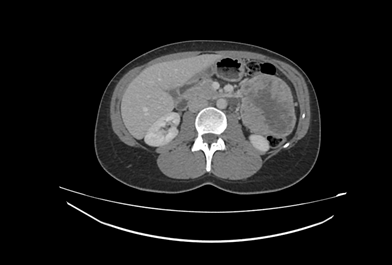

TAC abdominal: masa en flanco izquierdo de 8,8 cm que parece depender de la cuarta porción duodenal y plantea como primer diagnóstico diferencial un GIST.

El TAC abdominal confirma la sospecha diagnóstica de tumor del estroma gastrointestinal (GIST), se deriva a la paciente a cirugía general con carácter urgente, donde se completa el estudio con una esofagastroduodenoscopia y se presenta el caso en el comité de tumores.